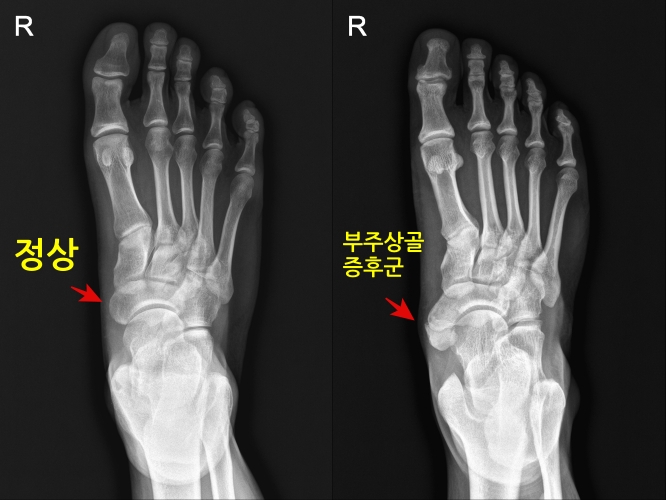

- X-ray, CT : 부주상골 존재여부 및 형상 확인

주상골의 내측에 발생하여 부주상골이라고 불리며, 전체 인구의 2~14%가 존재하는 선천성 질환입니다.

부주상골은 발의 내측에 위치한 주상골에 붙어있는 부골입니다. 부주상골은 섬유조직 또는 연골로 주상골에 연결되어 있지만 유합이 되지 않은 상태입니다.